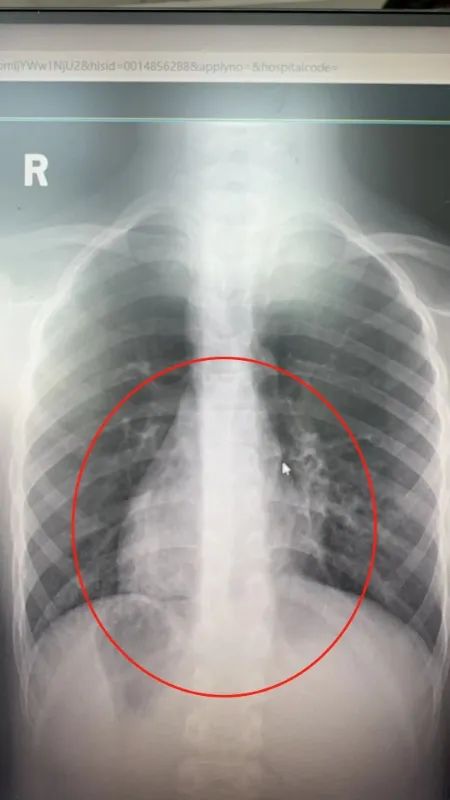

“镜面人”的心脏在靠右的位置。

“镜像人”在医学上称之为“全内脏反位”,指的是人体内部脏器的位置左右颠倒。比如一般人都是心脏在左侧,肝胆在右,而“镜像人”的内脏生理功能正常,只不过心脏在右,肝胆在左,就好像照镜子一样。“镜像人”的出现相当罕见,概率大约在百万分之一。

经过检查,小周患的是急性阑尾炎,需要接受手术治疗。影像结果同时显示,他的阑尾位于身体左侧,和正常人位于右下腹相反。这给手术带来了一定难度。